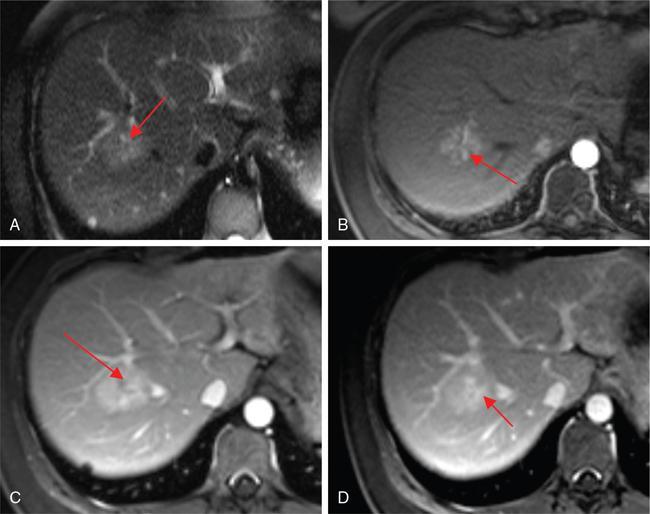

Ritu K. Kashikar, Shrinivas B. Desai, Pooja Punjani Vyas, Nilesh Doctor, Vivek Shetty Owing to advances in technology, focal liver lesions (FLLs) are increasingly encountered. Imaging particularly computed tomography (CT) and magnetic resonance imaging (MRI) play a vital role in diagnosis and characterization of FLL, thus avoiding unnecessary biopsies and interventions. Multiphase CT accurately diagnosis most liver lesions. Better soft tissue contrast and lack of ionizing radiation makes MRI a preferred modality in diagnosing FLLs. MRI with or without contrast for characterization of liver lesions regardless of preexisting liver disease has been assigned the highest rating as per American College of Radiology Appropriateness Criteria (Table 9.11.1). Solid lesions of epithelial origin Solid lesions of nonepithelial origin Pitfalls Cystic liver lesion Developmental cyst Infective cyst Miscellaneous Tmours of hepatocellular origin Tumours of nonepithelial origin Malignant cystic lesion Hepatic metastasis Ultrasound is often the initial modality for diagnosis and also the incidental detection of FLLs. Limitations to USG include the detection of small lesions less than 2 cm in size, particularly in patients who are cirrhotic or undergoing chemotherapy. Characterization of FLLs, involvement of crucial structures such as blood vessels, local staging and decisions such as operability are also not accurate with ultrasound alone and require confirmation with CT/MRI. The liver typically images in supine and left lateral positions. A curvilinear transducer with a frequency of 1.5 Hz is used. The subcostal diagonal, subcostal longitudinal or sagittal and transverse right intercostal lateral views are used. Right lobe of liver is imaged through an intercostal approach when the patient is taking deep inspiration. Subcostal view is used to image the three hepatic veins in one view. Transverse, longitudinal and oblique views of the liver are taken to image all the segments of liver. Colour and power Doppler have increased sensitivity for FLL detection, but sensitivity is still inferior to contrast-enhanced CT and MRI. The introduction of microbubble contrast agents (CAs) and the development of contrast-specific techniques have opened new perspectives in ultrasound of the liver. The technique is based on a new class of intravascular microbubble agents which contain perfluoro gases instead of air. This when combined with scanning modes sensitive to harmonic responses of microbubbles enable tissue signal suppression. The advent of the multislice technique and isotropic voxel have improved the spatial resolution of CT, allowing the recognition of small FLLs in difficult areas. Multislice CT has a sensitivity and specificity in the diagnosis of malignant FLLs of 63% and 64%, and 92 and 97%, respectively. Contrast media administration with dose based on the patient’s weight (approximately 600 mg iodine/kg of bodyweight), an iodine content of 350–400 mg/mL and a high injection rate of 4–5 mL/s are imperative to attain good contrast enhancement. Region of interest in the abdominal aorta and a threshold of 100 HU allows correct timing for threshold. A delay of approximately 18 s after the threshold provides the first arterial phase, allowing detection of hypervascular FLLs such as hepatocellular carcinoma (HCC). The late arterial phase is obtained approximately 10 s after the early arterial phase and shows progressive enhancement of hypervascular lesions, improving detection rate, while the optimal hepatic enhancement in the portal phase is reached approximately 50–60 s after the threshold. Portal venous thrombi are also best detected in this phase. The venous phase aids in the detection of washout, hepatic venous thrombosis. Delayed phase is often required in lesions such as cholangiocarcinoma and haemangioma, which show progressive enhancement (Table 9.11.2, Fig. 9.11.1). Delayed phase images are required for tumours such as cholangiocarcinoma and large haemangiomas, which reveal delayed enhancement. As mentioned previously, MRI is the modality of choice in diagnosis of FLLs. Most FLLs appear hyperintense on T2W1 images with varying intensity depending upon the water content and flow dynamics. FLLs are typically hypointense on T1W1 images with the exception of fat containing, haemorrhagic lesions and those containing chelates of metals like regenerating/dysplastic nodules. In- and opposed-phase images help in detection of intralesional fat. Diffusion-weighted images are beneficial particularly in noncirrhotic population and best suited in detection of metastasis. Postcontrast images obtained with extracellular agents are parallel to those obtained with CT (Fig. 9.11.2). The pre- and postcontrast MRI protocol is mentioned in Table 9.11.3. T2-weighted single-shot fast spin-echo (SE) T1-weighted in- and opposed-phase GRE Dynamic 3D T1-weighted FS spoiled GRE (in hepatic arterial, portal venous and equilibrium phases) There are two main categories of CAs used in liver imaging – the extracellular and the hepatocyte-specific (Fig. 9.11.3). Extracellular agents are more widely used and provide information similar to contrast-enhanced CT study. The advantage of the other category of CAs, that is, hepatocyte-specific agents, is the ability to provide this extracellular information with added benefit of delayed phase information. Tumours of hepatocellular origin with functioning hepatocytes take up and biliary excretion with take up and retain these agents appearing isointense to background liver. Lesions without functioning hepatocytes fail to retain contrast and hence appear hypointense to background liver on delayed phase. This allows better detection and characterization of focal liver lesion particularly those lesser than 2 cm (Table 9.11.4). Haemangioma is the most common benign hepatic tumour. The incidence in general population varies from 1% to 20%. Females have a higher preponderance with variable female to male ratios of 2:1 to 5:1. Imaging in particular MRI has high reliability in diagnosing classic haemangioma. The sensitivity and specificity of MRI is greater than 90% in diagnosis. The aetiology of haemangioma is unknown. Since haemangiomas are known to run in families, a genetic origin has been implicated, while other mesenchymal tumours are thought to be congenital. Most patients are asymptomatic and often the lesion is discovered as an incidental finding. Pain in the right upper abdomen is the most common complaint; others include loss of appetite, nausea, vomiting and abdominal discomfort. Symptoms are usually seen in large haemangiomas or those with complications. Liver function tests and tumour markers like AFP and CA19.9 are within normal limits. Blood-filled cavities of varying sizes lined by flat endothelial cells and supported by fibrous connective tissue are seen on histology. Three histological subtypes have been described: the capillary haemangioma, the cavernous haemangioma and the sclerosing haemangioma. The imaging features of a haemangioma depend on its size; typical haemangiomas are mostly less than 3 cm in diameter. Haemangiomas are hyperechogenic, homogeneous lesion presenting a posterior acoustic enhancement (Fig. 9.11.3). The hyperechogenicity of haemangiomas is related to the interfaces between vascular spaces, fibrous stroma and the slow blood flow. Typically, haemangiomas have slow flow and hence do not show vascularity on colour or power Doppler. The sensitivity and specificity of ultrasound in differentiating haemangioma from other malignant lesions are high, with values of approximately 94.1% and 80%, respectively, for lesions less than 3 cm in diameter. Unlike HCC, no flow is seen on colour Doppler. A peripheral echogenic rim around hypoechoic lesions can suggest haemangioma. On the contrary, perilesional hypoechoic rim called the target sign is seen in lesions such as metastasis (Table 9.11.5). Adenomas can be distinguished on the basis of the absence of posterior acoustic enhancement and characteristic pattern of peripheral vascularity seen in adenoma. Another differential diagnosis to be considered is focal nodular hyperplasia (FNH), which has the characteristic ‘spoke-wheel sign’. Contrast-enhanced ultrasound (CEUS) improves specificity for the diagnosis of haemangioma. The vascularity pattern with contrast-enhanced USG is similar to that seen with CT. The typical hemangioma (HH) shows peripheral nodular enhancement in the arterial phase with complete (but sometimes incomplete) centripetal filling in the portal venous and late phases. This particular pattern of enhancement helps in differentiating haemangiomas from other lesions like adenomas, FNH, HCC or metastasis. This characteristic enhancement pattern has a sensitivity of 98% for histologically proven HH. One should be aware that an HH can rarely have a centrifugal enhancement. Computed tomographic (CT) findings consist of a hypoattenuating lesion on nonenhanced images. Haemangiomas show peripheral discontinuous nodular enhancement on arterial phase of dynamic contrast-enhanced CT. The density of the nodules is equivalent to that of the aorta. Centripetal filling with is seen on venous phase, which progresses to uniform enhancement. The enhancement persists on delayed phase (Fig. 9.11.4). Washout of contrast on delayed phase is not seen in haemangioma and if seen, alternate diagnosis must be considered. This classical pattern of enhancement cannot be highlighted in very small lesions of less than 5 mm, which can be difficult to characterize. In patients with severe fatty infiltration of the liver, HH can appear hyperdense relative to the adjacent liver parenchyma on nonenhanced scan. Haemangiomas are hyperintense on T2-weighted images, which is identical to that of cerebrospinal fluid. T2 hyperintense signal is classically described as ‘light bulb bright’. Malignant lesions of the liver do not appear as bright on T2W1 images. They appear hypointense to adjacent liver on T1-weighted images. Long relaxation T2W1 images further improve accuracy in diagnosis of haemangiomas and help in differentiation from metastasis. Haemangiomas, unlike other liver lesions retain hyperintense signal on long relaxation T2W1 images. A threshold of 112 ms has 92% accuracy, 96% sensitivity and 87% specificity for differentiating haemangiomas from metastasis. On gadolinium administration, the enhancement pattern is similar to that seen with iodinated contrast on CT. Classic enhancement pattern in combination with characteristic T2 appearance are diagnostic for haemangioma (Fig. 9.11.5). Certain pitfalls exist in diagnosing haemangiomas using gadoxetate disodium. Due to the lack of hepatocytes, haemangiomas appear hypointense to the background liver on delayed hepatocyte phase and mimicking malignant process (Table 9.11.6). Lesions shown peripheral nodular arterial enhancement (Table 9.11.7): On fluorodeoxyglucose-positron emission tomography (FDG-PET)/CT, most hepatic haemangiomas appear low-attenuation lesions with FDG avidity equal to background liver parenchyma and are easily determined to be benign. However, a small percentage of haemangiomas may be FDG-avid. If an FDG-avid hepatic lesion demonstrates the characteristic enhancement pattern, this is consistent with an FDG-avid haemangioma. Technetium-99m pertechnetate-labelled red blood cell scintigraphy has high specificity in the diagnosis of haemangiomas. In this technique, there is decreased activity in haemangiomas on early images and increased activity on delayed blood pool images. Therefore, radionuclide scintigraphy has a sensitivity of 78% and an accuracy of 80% and may be a valuable tool when the diagnosis cannot be achieved with other imaging modalities. Large haemangiomas are often heterogeneous with internal clefts and septae. They are termed as giant haemangiomas when they exceed 4 cm in diameter. Discrepancies are there in definition with some authors defining giant haemangiomas as lesions greater than 6 cm or 12 cm in diameter. These may cause symptoms of abdominal pain and distension. These haemangiomas demonstrate changes such as haemorrhage, thrombosis, extensive hyalinization, liquefaction and fibrosis. The central cleft-like area may be due to cystic degeneration or liquefaction. On USG, they reveal heterogeneous echotexture. They are hypoattenuating and heterogeneous on nonenhanced CT with central areas of low attenuation. After intravenous administration of contrast material, the typical early, peripheral and globular enhancement is observed. These may show irregular or ‘flame-shaped’ discontinuous peripheral enhancement as opposed to typical nodular enhancement pattern seen in smaller haemangiomas. Although centripetal pattern of enhancement is seen during the venous and delayed phases, the filling-in incomplete. Central scars are defined in this subset of haemangiomas (Fig. 9.11.6). At MRI, T2-weighted images show a markedly hyperintense cleft-like area and some hypointense internal septa within a hyperintense mass. On delayed phase, incomplete filling and central scar are seen similar to CT (Fig. 9.11.7). Complications include intratumoural haemorrhage, inflammatory changes or consumptive coagulopathy (Kasabach–Merritt syndrome). These may warrant management such as arterial embolization or resection. This pattern is seen 16% of all haemangiomas, and is seen more often in small haemangiomas (42% of haemangiomas) <1 cm in diameter. CT and MRI show immediate homogeneous enhancement at arterial phase CT or contrast-enhanced MRI. The size of the blood spaces is the reason for difference in enhancement pattern. Smaller the lesion, smaller the size of blood spaces and faster the rate of spread of contrast material. These lesions usually show perilesional halo of hyperenhancement on the late arterial phase, which is believed to be due to arteriovenous shunting. Rapid arterial enhancement makes these haemangiomas difficult to distinguish from hypervascular metastasis (Table 9.11.8). However, washout of contrast is seen from haemangiomas on delayed phase (Fig. 9.11.8). Hepatic haemangiomas rarely demonstrate calcifications, while haemangiomas in other locations frequently demonstrate phleboliths. Calcified haemangiomas are mostly found incidentally. Calcifications may occur in the marginal or central portion of the lesion and consists of multiple spotty calcifications, which correspond to phleboliths. However, large, organized calcifications are also possible. Some calcified haemangiomas may demonstrate poor enhancement. Hyalinized hepatic haemangiomas are rare. It has been suggested that hyalinization represents an end stage of haemangioma evolution. These haemangiomas are usually asymptomatic. The radiological features of a haemangioma are completely altered ones hyalinization occurs; hence biopsy is often mandatory for diagnosis. Hyalinized haemangiomas show only slight high signal intensity on T2W1 images. There is lack of early enhancement on dynamic contrast-enhanced images (Fig. 9.11.9). Fluid–fluid levels within haemangiomas are very rare. Fluid–fluid levels are seen both with CT and MRI with inferior layer representing the red blood cells and superior layer unclotted serous blood. Dependent hyperdensity/T1 hyperintensities can be seen corresponding with dependent haemorrhage. Pedunculated haemangiomas are very rare. They can be asymptomatic or complicated by subacute torsion and infarction. Typical enhancement pattern and signal on T1 and T2W1 images are clues to the diagnosis. Capsular retraction is usually associated with malignant tumours such as cholangiocarcinoma, epithelioid haemangioendothelioma or metastases. Rarely, it has been seen in haemangiomas. A possible mechanism could be fibrous degeneration. Multiple haemangiomas are seen in 10% of cases and usually show classical imaging features. Fatty infiltration of liver may alter the imaging appearances of lesions. Haemangiomas appear slightly hyperechoic, isoechoic or hypoechoic relative to the fatty liver. At nonenhanced CT, the lesion may be hyperattenuating relative to the liver. Contrast-enhanced CT shows peripheral enhancement and delayed filling, an appearance similar to that of a haemangioma in a normal liver. Haemangiomas are less common in setting of cirrhosis and may be difficult to diagnose due to sclerosis. Complications are seen in 4.5%–19.7% and often seen in large lesions such as inflammation, coagulation within can lead to systemic disorders, haemorrhage would lead to haemoperitoneum, volvulus and adjacent organ compression. Irrespective of the size, treatment is indicated only for haemangiomas with significant symptoms, those developing complications, or when there is an inability to exclude malignancy. Attempt should be made to exclude other causes of the patient’s symptoms. The term focal nodular hyperplasia (FNH) was introduced in 1958 by Edmondson. In 1995, the International Working Party classified FNH with other regenerative lesions, and not a neoplastic lesion. It is defined as a nodule consisting of normal appearing hepatocytes occurring in a histologically normal liver. It is the second most common tumour of the liver after haemangioma with a reported prevalence of 0.9%. The lesion is more commonly seen in females with female to male ratio of 8:1. Multiplicity is seen in 20% of patients. The combination of multiple FNH lesions and haemangiomas is considered to be multiple FNH syndrome. Vascular malformation and vascular injury have been suggested as the underlying mechanism. An association with steroids has been denied more recently. FNH has been classified as classic and nonclassic varieties. These have been discussed in Table 9.11.9. Classic FNH is characterized by abnormal nodular architecture, malformed vessels and cholangiolar proliferation. Nonclassic FNH lesions lack one of the following classic features – nodular abnormal architecture or malformed vessels – but always show bile ductular proliferation. Classic FNH on gross appearance shows lobulated contours with multiple nodules surrounded by fibrous septae originating from a central scar, which contains a vascular malformation. On histopathology, nodular hyperplastic parenchyma is seen in classic FNH. Circular or short fibrous septae surround these nodules completely or incompletely. Thickening of the hepatic plates is seen. Fibrous connective tissue, cholangiolar proliferation with surrounding inflammatory infiltrates and malformed arteries, capillaries, vascular channels of undetermined type and veins are seen in the central scar. The arterial blood in FNH shows centrifugal distribution from anomalous central arteries. Fatty infiltration is seen in approximately 50% of lesions, while signs of hepatic steatosis are seen in approximately 20% of cases with classic FNH. Variable amounts of Kupffer cells are seen in both classic and nonclassic variants. Nonclassic FNH is heterogeneous and on gross appearance resembles adenomas in most cases, with vaguely lobulated contours and lack of a macroscopic central scar. The histology varies with subtypes. Subtypes of nonclassic FNH include telangiectatic type, mixed hyperplastic and adenomatous forms and FNH with cytologic atypia. The histological features of these are described in Table 9.11.10. At US, typical FNH is often not well visualized. The lesions may be slightly hypoechoic, isoechoic or slightly hyperechoic. The compressed liver tissue form a hypoechoic halo around the lesion, which appears more prominent in patients with fatty infiltration. A prominent central scar may improve the conspicuity of the lesions. Use of colour and power Doppler US shows vascularity in suspected FNH. On contrast-enhanced USG, FNH is hyperenhancing in the arterial and portal venous phases in more than 90% of cases. The arterial enhancement patterns include central (60%–70% of cases) or eccentric (<20% of cases) with centrifugal filling, but sometimes are homogeneous. Multiphase CT is an excellent modality for detection and characterization of FNH. These lesions classically show a lobulated contour. At unenhanced CT, the lesions are either hypoattenuating or isoattenuating to the surrounding liver. In the arterial phase, the lesions show homogeneous intense enhancement except the central scar and fibrous septa. In the portal and later phases, the lesions become more isoattenuating with the surrounding liver. The central scar reveals enhancement on delayed phase (Fig. 9.11.10). This feature helps distinguish from other lesions with central scar-like fibrolamellar carcinoma. A vascular malformation can be seen in the central scar in some cases (Fig. 9.11.11). There may be enlarged hepatic veins in the vicinity of the mass. FNH do not have portal venous drainage. The drainage is essentially into hepatic venules, hence the enlarged adjacent veins. The central scar is often not identified in small FNH lesions. In a study, 80% of FNH lesions less than 3 cm lacked visible central scar. The sensitivity and specificity of MRI in diagnosis of FNH are 70% and 98%, respectively. The central scar is more often detected with MRI than with CT (78% and 60%, respectively). FNH is typically iso- or hypointense on T1-weighted images (94%–100%) and is slightly hyperintense or isointense on T2-weighted images (94%–100%). The lesions may not be very conspicuous on T2W1 images. The central scar is hyperintense on T2-weighted images in 84% of cases. FNH shows intense homogeneous enhancement in the arterial phase. The enhancement pattern in arterial phase may be nodular, resembling a popcorn, the result of intralesional fibrous septae. Mosaic pattern of heterogeneous enhancement seen in malignant lesions is not seen in FNH. Central vascular malformation may be seen in early phases. These lesions classically fade to isointensity on delayed phase with the exception of the central scar (Fig. 9.11.12). FNH may show a pseudocapsule, which results from compression of the surrounding liver parenchyma by the FNH, perilesional vessels and inflammatory reaction. The pseudocapsule may show enhancement on delayed contrast-enhanced images. A central scar is present at imaging in most patients with FNH. The central scar is hyperintense on T2W1 and hypointense on T1W1 images. The presence of inflammation and vessels within the scar are responsible for the hyperintense signal (Fig. 9.11.13). The scar does not enhance on early phases of contrast study and shows enhancement on delayed phases of dynamic study. The scar is absent in 30% of cases. The hepatocyte-specific CA gadoxetate disodium can be useful in distinguishing FNH from other lesions like adenomas. Densely packed functioning hepatocytes and abnormal blind-ending bile ductules in FNH result in contrast retention and delayed biliary excretion. FNH often shows enhancement on delayed images using gadoxetate disodium, and along with radiating fibrous septae, it may result in a characteristic spoke-wheel appearance. On the contrary, hepatocellular adenomas (HCAs) are usually hypointense to liver on hepatocyte phase images because they lack bile ductules. Superparamagnetic iron oxide (SPIO) is a negative reticuloendothelial-specific CA taken up primarily by the hepatosplenic Kupffer cells. This agent shortens T2 relaxation time predominantly, leading to a significant decrease of SI of normal hepatic. FNH contains Kupffer cells and hence shows significant signal drop after administering SPIO. This CA is, however, not commonly used particularly with advent and increased usage of hepatocyte-specific agents (Table 9.11.11). These lesions have high signal intensity on T2-weighted images, a central scar with low signal intensity on T2-weighted images, a prominent pseudocapsule and incomplete intense enhancement of the lesion. Extreme heterogeneity can be seen in these lesions leading to difficulty in distinguishing from malignant lesions such as HCC and cholangiocarcinoma. Biopsy and histopathology diagnosis are often needed in this subset. Telangiectatic FNH may show areas of haemorrhage. A French study has reported an association of 23% between FNH and haemangiomas. The incidence of coexistence of FNH and adenoma is lower (3.6%). There have also been reports of rare associations of FNH with other types of vascular anomalies like congenital absence of the portal vein, inflammatory pseudotumours of the liver, hepatic vein thrombosis and intrahepatic arteriovenous shunting. Imaging differentials include HCA and other lesions with central scar like fibrolamellar carcinoma, HCC and giant haemangiomas (Table 9.11.12). FNH shows intense arterial phase enhancement and isodensity/isointensity on delayed phase, this feature helps in distinguishing from adenoma, which usually are hypoattenuating on the delayed phase. T1 hyperintensity seen in adenomas is not seen on FNH. Biopsy is recommended in cases where radiological features are atypical and distinguishing from malignant lesions like HCC cannot be made on the basis of imaging findings alone. As there is no risk of malignant transformation and complications are rare, FNH does not need treatment. Patients with large FNH causing compression of adjacent organs or occurrence of torsion in a pedunculated FNH may need surgical resection. Also, patients with diagnostic dilemma may be considered as surgical candidates. Adenoma is a less common benign primary neoplasm of the liver. Women of childbearing age taking oral contraceptives are considered at highest risk; however, it can occur in other women as well as men. Hepatic adenomas (HAs) were particularly associated with the use of older generation of OC pills with high-oestrogen content. Adenomas have also been reported to occur in men secondary to anabolic steroid/androgen use. Clomiphene, danazol and testosterone in patients with Fanconi anaemia (FA) and without FA, Klinefelter’s syndrome, glycogen storage disorders (GSDs) I, III and IV, alcohol and metabolic syndrome are other hormonal therapies and conditions associated with adenoma. Development of >10 adenomas in a patient is defined as hepatocellular adenomatosis (Fig. 9.11.14). Germline mutations of hepatocyte nuclear factor (HNF)-1 alpha and patients with type 3 maturity onset diabetes of young (MODY-3) may predispose. HCA has been categorized into three distinct subtypes based on genetic and pathologic features. These have been discussed in Table 9.11.13. Some exhibit both β-catenin activation and inflammatory features. Patients are usually asymptomatic at the time of diagnosis but some present with abdominal pain, haemorrhage, abnormal liver function tests or seldom with a palpable mass. HCA associated with haemorrhage may present with acute abdominal pain, elevated liver enzymes and hypovolemic shock. Signs of chronic anaemia and/or ‘systemic inflammatory syndrome’, characterized by fever, leukocytosis and elevated serum levels of C-reactive protein can be seen in patients with inflammatory HCA. Inflammatory HCAs are associated with a definitive increased risk of bleeding (>30%) and a risk of malignant transformation (5%–10%). The highest predilection for malignant transformation of all HCAs is seen in β-catenin activated subtype. On gross appearance, adenomas are well-circumscribed often encapsulated lesions with size varying between 1 and 30 cm. Lesions may be solitary or multifocal. They typically arise in nonfibrotic liver, however, the inflammatory subtype has been reported in the background of cirrhosis The cut surface of HA may be tan-yellow or red-brown depending upon the presence of steatosis or peliosis/haemorrhage/old haemorrhage, respectively. Sheets of benign-appearing hepatocytes with interspersed thin-walled, unpaired arteries are classically seen in HCA. Other variable features are steatosis, inflammatory cell infiltrate, sinusoidal dilatation, myxoid changes and presence of pigments such as bile pigment, lipofuscin or Dubin–Johnson-like pigment (Table 9.11.14). The typical small HCA is isoechoic in comparison to the surrounding liver parenchyma. Adenomas with high lipid content are hyperechoic on ultrasound. Intratumoural haemorrhage can also result in increased echogenicity and heterogeneity, or cystic areas. Calcifications are seen as hyperechoic foci with acoustic shadowing. Peripheral peritumoural vessels and intratumoural vessels with a flat continuous or triphasic form are seen on colour Doppler. FNH does not show this pattern of vascularity and hence this finding may be useful in distinguishing the two disease entities. On contrast-enhanced USG, arterial phase reveals centripetal or diffuse enhancement. Telangiectatic HCA with or without inflammation typically exhibit iso- or hyperenhancement in comparison to the surrounding liver parenchyma. Hypoenhancement is seen in portal venous phase with delayed washout in all subtypes. USG and contrast-enhanced USG features of histologic subtypes have been described. HNF-1α-inactivated HCAs are hyperechoic due to fat content and may be misdiagnosed as haemangiomas. The enhancement pattern is however that of arterial enhancement. With venous washout in contrast to haemangiomas which show portal venous hyperenhancement. On CEUS, telangiectatic HCA with or without inflammatory changes shows central multilocular vessel supply similar to FNH. These lesions might show centrifugal hyperenhancement during the early arterial phase which may persist on portal venous phase. Nevertheless, most adenomas are not specifically diagnosed at US and are usually further evaluated with CT or MRI. Multiphase CT is a good diagnostic modality in diagnosis of HCA. Fat or haemorrhage can easily be identified on unenhanced images. CT evidence of fat within the adenoma is seen in only about 10% of cases. Lesions show strong arterial enhancement and subcapsular feeding vessels. Enhancement is more heterogeneous in larger tumours and those with internal haemorrhage. The enhancement usually does not persist in adenomas because of arteriovenous shunting (Fig. 9.11.15). MRI is the modality of choice in diagnosis of adenomas and distinguishing various subtypes. Although the lesions can reveal varying signal on T1W1 images, recent reports have suggested that most adenomas are bright on T1-weighted images, 77% of cases in a study by Paulson et al. Other studies have, however, lesser incidence of T1 hyperintensity varying from 35% to 59%. Heterogeneous signal on TW1 images may be due to areas of increased signal intensity resulting from fat (36%–77% of cases in different series) and haemorrhage (52%–93%). Forty-seven to seventy-four per cent of HCAs are predominantly hyperintense relative to liver on T2-weighted images (Fig. 9.11.16). Majority of lesions are, however, heterogeneous owing to areas of haemorrhage and necrosis. Contrast-enhanced dynamic MR study shows early enhancement with peripheral subcapsular vessels. MR appearances can vary depending on the histological subtype (Table 9.11.15). On plain MRI, inflammatory HCA is often hyperintense on T2W images and hypointense on T1W sequence corresponding to areas of sinusoidal dilatation and inflammatory infiltrates. Foci of fat appear as areas of signal drop on opposed-phase images. They are hypervascular masses with persistent enhancement on dynamic study. Variable update of contrast especially at the periphery may be seen on hepatobiliary phase. Marked T2 hyperintense signal with persistent delayed enhancement has high sensitivity and specificity of 85% and 87%, respectively, for the diagnosis of inflammatory subtype. Peripheral hyperintensity on T2W1 images reflects the abnormal ductal reaction with altered biliary excretion and has been described as ‘atoll sign’ (Fig. 9.11.17).

MR

Haemangiomas